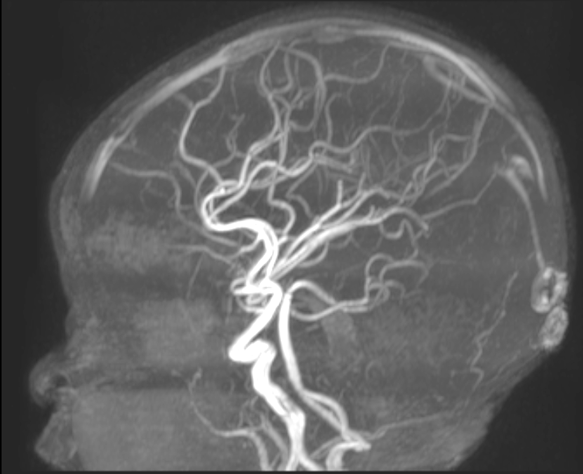

“Instead of traditional surgery, which would have required opening her skull and cutting connections in her brain, this approach allowed us to work through her blood vessels, minimizing risks and recovery time,” explains Dr. Prakash Muthusami, an interventional neuroradiologist at SickKids who led the eventual series of procedures and leads the hospital’s Neurointerventional Program.

As opposed to an open surgical procedure, the endovascular approach involves using catheters introduced inside blood vessels to selectively block blood flow to the abnormal areas of the brain, effectively “disconnecting” the problematic hemisphere while preserving healthy tissue.

The technique essentially targets dysfunctional areas of the brain, and by cutting the connection, protects the functioning half of the brain.

Between February and April 2024, four carefully planned embolization procedures, spaced two to three weeks apart, successfully isolated Maryam’s left hemisphere.

And at every step, the Interventional Neuroradiology team, Epilepsy and Neurosurgery teams worked together, using detailed electroencephalogram (EEG) and brain MRI scans to ensure precision and safety.